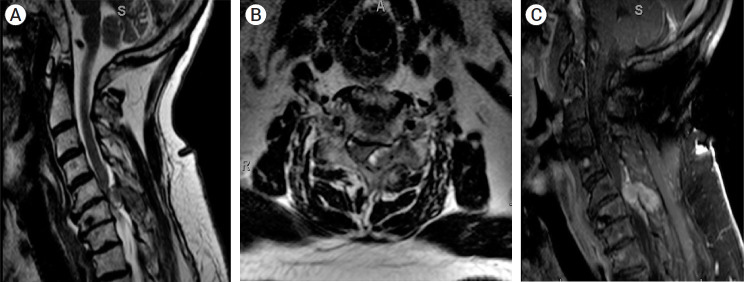

这是一例独特的颈椎转移性嗜铬细胞瘤病例,患者在术前接受了栓塞治疗,随后进行了全切。一名 65 岁的男性患者患有转移性嗜铬细胞瘤,两周前出现颈部疼痛加重、左臂和左腿无力和麻痹以及尿失禁。磁共振成像显示,C6 处有转移性骨质病变,并伴有严重狭窄和脊髓压迫。患者术前使用液体栓塞剂成功进行了血管栓塞,随后进行了C5-C7椎板切除术、肿瘤全切术和C3-T2后路脊柱融合术。术后六周,患者表示体力有所改善,颈部疼痛和麻痹症状也得到了缓解。虽然目前还没有治疗颈椎转移性嗜铬细胞瘤的标准范例,但术前栓塞可以最大限度地减少术中失血和随后手术切除时血流动力学的不稳定。

This is a unique case of metastatic pheochromocytoma of the cervical spine treated with preoperative embolization and subsequent en bloc resection. A 65-year-old man with metastatic pheochromocytoma presented with two weeks of worsening neck pain, left arm and leg weakness and paresthesia, and urinary incontinence. Magnetic resonance imaging showed a metastatic osseous lesion at C6 with severe stenosis and spinal cord compression. The patient underwent successful preoperative angiographic embolization with a liquid embolic agent followed by C5-C7 laminectomy, en bloc tumor resection, and C3-T2 posterior spinal fusion. Six weeks postoperatively, the patient reported improving strength and resolving neck pain and paresthesias. While there is no standard paradigm for the treatment of metastatic pheochromocytomas of the cervical spine, preoperative embolization may minimize intraoperative blood loss and hemodynamic instability during subsequent surgical resection.